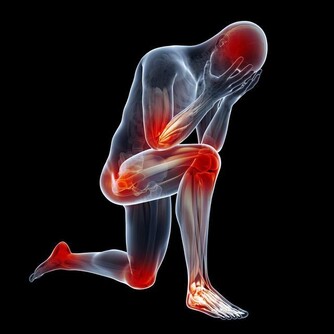

腎臟不像胃,稍有不舒服就有反應,它在早期受到損害時,一般患者不會有明顯的症狀,僅有疲勞、乏力等不適,往往會被患者忽視。所以,對於上述三類高危人群,不管有沒有出現症狀,都建議每年查1-2次腎臟B超,以時刻監測腎臟情況。